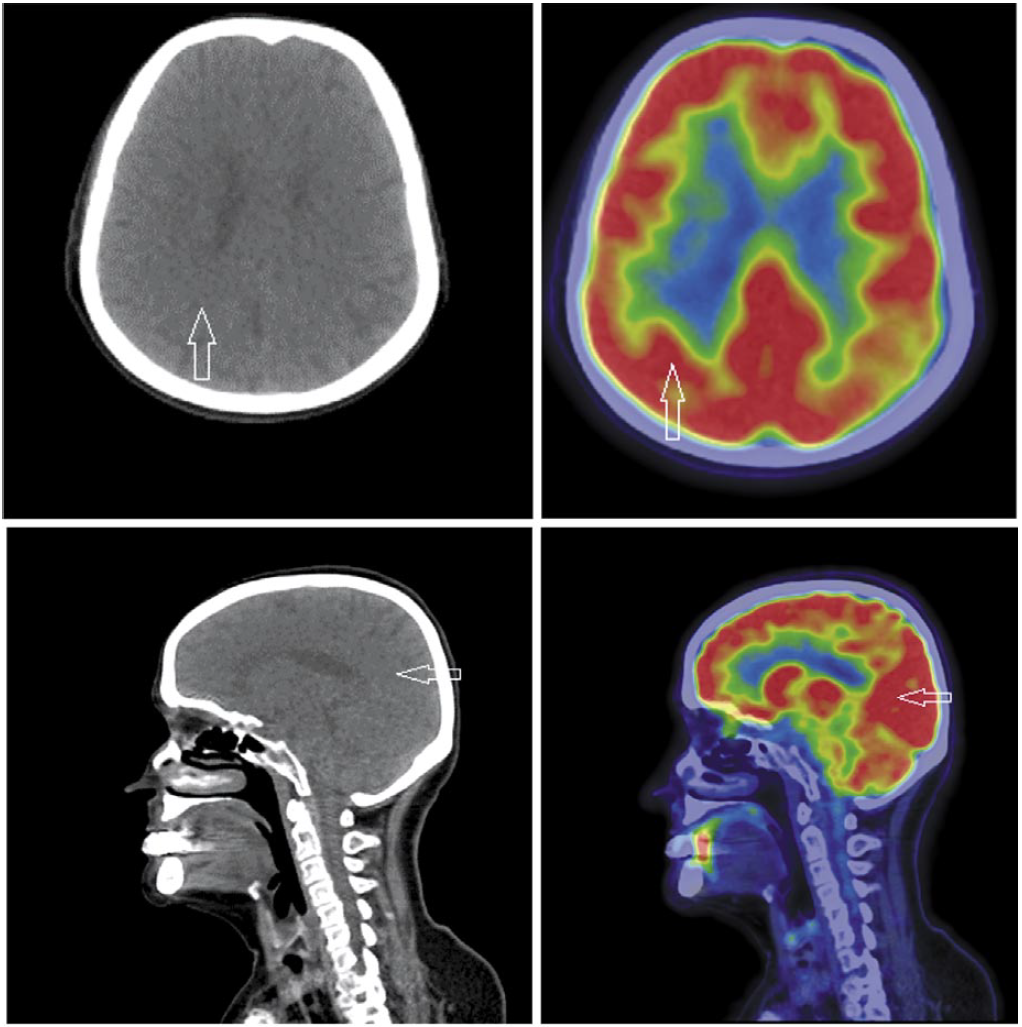

По данным позитронно-эмиссионной томографии (ПЭТ)/КТ в послеоперационной области – без очаговой фиксации радиофармпрепарата. Дополнительные образования в области таза не визуализируются. Паховые и тазовые л/у не увеличены. Очагов патологического метаболизма фтордезоксиглюкозы не выявлено.

Через 5 мес выполнена ПЭТ/КТ с использованием 18-фтордезоксиглюкозы. Достоверных данных о наличии активного специфического процесса не выявлено (рис. 3).

Рис. 3. Больная С., 62 года. На аксиальных и сагиттальных ПЭТ/КТ проекциях очагов патологической фиксации радиофармпрепарата на фоне физиологического метаболизма не выявлено.

Fig. 3. Patient S., 62 years old. On axial and sagittal PET/CT projections, the parts of pathological fixation of radiopharmaceuticals against the background of physiological metabolism have not been revealed.

Приведенный случай свидетельствует о редком метастазировании рака вульвы в ГМ при отсутствии других признаков прогрессирования заболевания. Проведенная лучевая терапия (ЛТ) в режиме тотального облучения ГМ СОД 30 Гр позволила достичь полной регрессии опухоли. При проведении дифференциальной диагностики солитарного поражения ГМ необходимо помнить о возможности метастазирования рака вульвы.